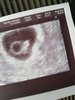

Dziewczyny jestem po wizycie, widziałam pulsujace serduszko był że mną mąż i syn 8 lat jeszcze nigdy nie widziałam żeby się tak stresowal.

Następna wizyta 4 czerwca, na razie termin na 9 stycznia.

Mam już założona kartę ciąży, lekarz wręczając mi ja powiedział "gratuluję jest pani już oficjalnie w ciazy"

Cieszę się strasznie

W załączniku wrzucam kropka